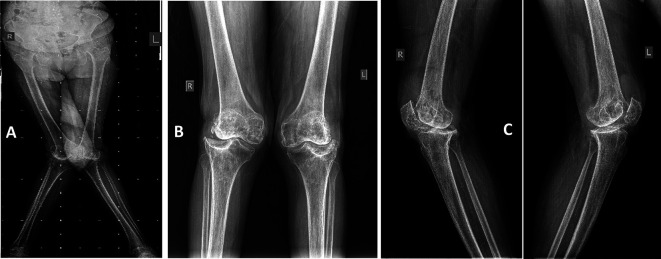

Methods: This prospective study was conducted on patients with moderate to severe grade valgus knee deformity who underwent RATKA from August 1, 2020 to May 31, 2022. Of 873 primary RATKA cases, 48 cases had valgus knee deformities. Among these, 27 had grade 2-3 valgus with intact medial collateral ligament (MCL), two had grade 3 valgus with incompetent MCL, 14 had grade 1 valgus, and five had post-traumatic valgus deformities. Over a two-year follow-up period, functional outcomes were assessed using the Western Ontario and McMaster Universities Osteoarthritis Index (WOMAC) and Knee Society Score (KSS), and complications were documented; however, radiological outcomes were not analyzed.

Results: Among 27 patients with Grade 2-3 valgus, the final cohort included 21 patients (24 knees). The mean age was 58.33 ± 9.63 years and 70.8% were female. Ten (41.7%) patients had rheumatoid arthritis and 14 (58.3%) had degenerative osteoarthritis (OA). The median surgical time was 68.00 (13.00) minutes, and the median blood loss was 478.45 (176.25) mL. The valgus grade was reduced from a baseline value of 22.43 ± 7.05 degrees to 5.26 ± 1.53 degrees at 6 weeks. The WOMAC scores improved from 67.58 ± 7.27 at baseline to 1.38 ± 0.57 in the second year post-operatively. Similarly, the KSS scores improved from 26.67 ± 10.34 at baseline to 181.96 ± 7.20 in the second year. One patient sustained a Type II supracondylar femur fracture after a fall, managed with distal femur arthroplasty, while another had delayed tibia pin tract healing, treated with antibiotics and dressings.